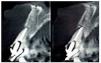

Figura 6. Tomografía computarizada de control realizada a los 6 meses.

Figura 11. Tomografía computarizada de control realizada a los 6 meses.